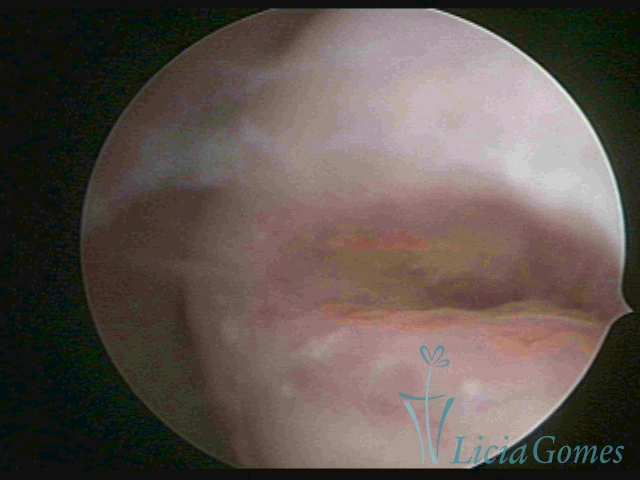

First part or proximal section or lower section:

During the proliferative phase, a light, crystalline mucus with a low adherence to the scope is found. The crypts and buds are a little swelled and vascularized, microvesicular, resembling grape clusters.